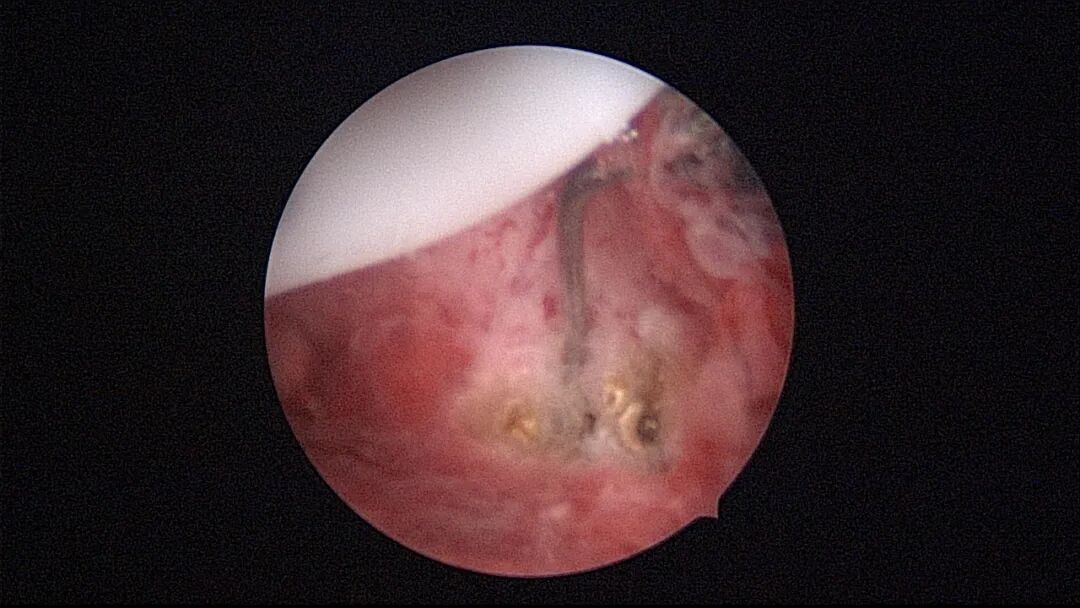

带环受孕图片

带环受孕节育环下移并嵌顿于切口憩室(详见“宫腔镜探秘带环受孕”,好孕空间2023年06月02日发布)

终止妊娠后宫腔很大,固定的节育环就像一叶扁舟